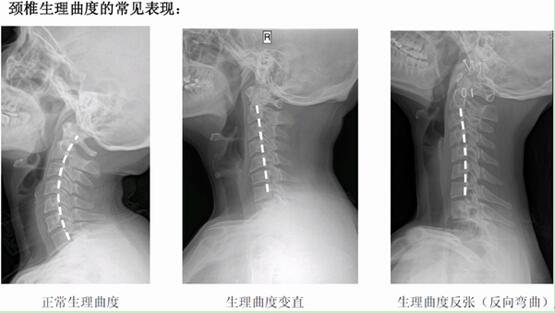

人的一生中有三分之一的時間在睡眠中度過,選個什么樣的枕頭好呢?日前,首都醫(yī)科大學(xué)附屬北京中醫(yī)醫(yī)院傳統(tǒng)療法門診主任馬彥旭在“人民好醫(yī)生”客戶端在線科普問診時表示,人的頸椎存在天然的生理屈曲,這個曲度的重要作用就是對頸椎的受力起到一定的緩沖作用,選對枕頭可以預(yù)防頸椎病。

馬彥旭解釋說:“很多頸椎病患者表現(xiàn)為頸椎生理屈曲減少或者消失。他們最典型的表現(xiàn)就是感覺脖子很累或者僵硬!币虼耍偨Y(jié)了三個挑選枕頭的要點: